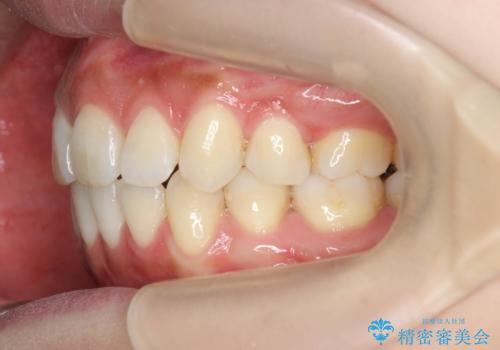

前歯をしっかりと後方に引いたことで、唇は閉じやすくなり、仕上がりに満足いただくことができました。